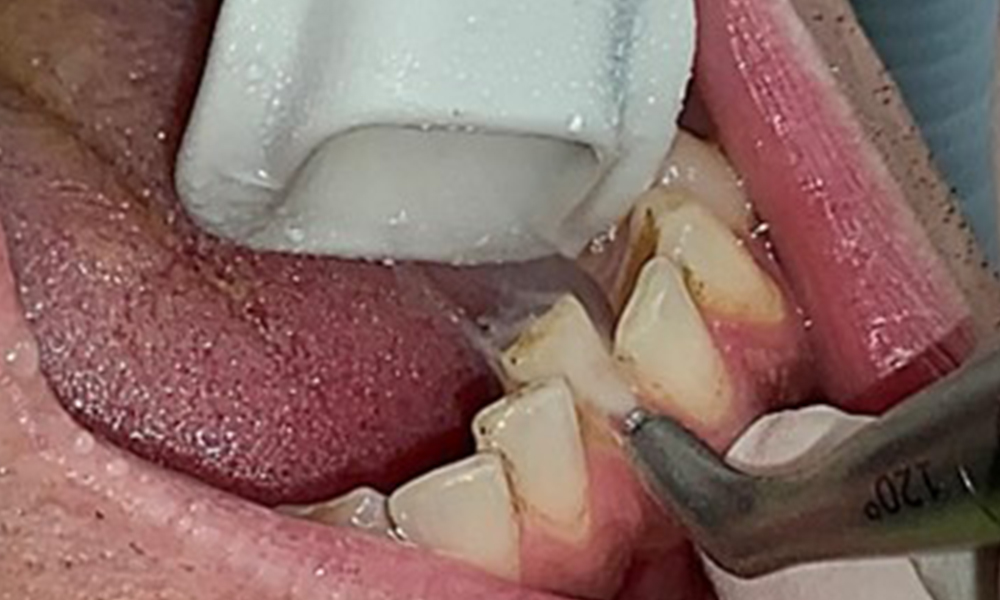

Instruction and motivation are important components of these appointments. Good home-based intraoral hygiene behaviour and understanding are important for patients. Plaque accumulation is particularly evident in the cervical regions (Fig. 8).

These must be discussed with the patient, and improvements to the teeth-brushing technique must be practised. A soft toothbrush attachment is recommended for home-based intraoral hygiene due to the presence of erosions and attritions.